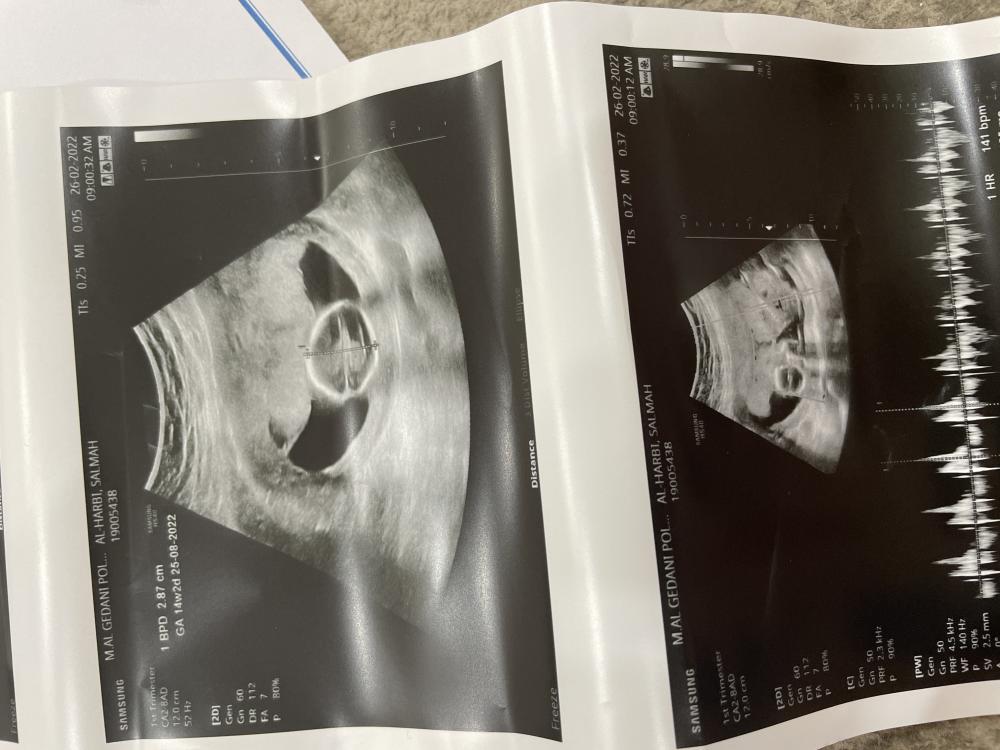

السلام عليكم رحت مستوصف خاص بعرف جنس الحنين واخرتها تقول مو باين بنزل الصور والا تعرف تقلي

مع الاسف الصوره مو موضحه وش بين الارجل